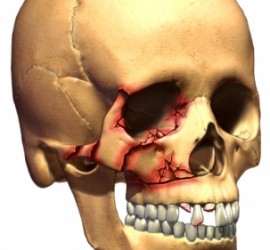

Этиология и патогенез. Занос туберкулезной палочки в кости лицевого скелета током лимфы или крови из очага поражения (чаще в легких). Не исключено первичное возникновение заболевания благодаря проникновению инфекции из очагов периодонтита зубов, при травме слизистой оболочки полости рта. Клиническая картина. Наличие вялотекущего воспалительного процесса в области той или иной кости […]